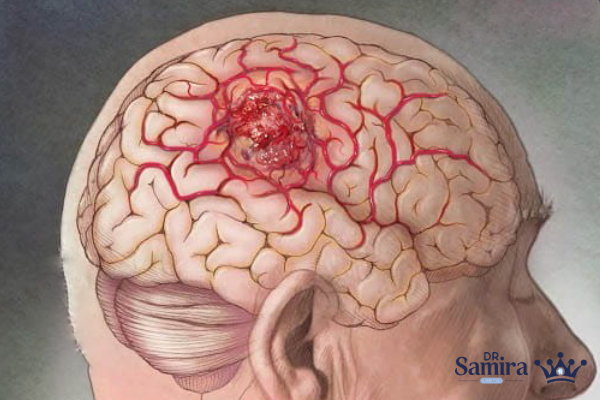

لنفوم مغز نوعی سرطان بدخیم است که از لنفوسیتها، یعنی سلولهای اصلی سیستم ایمنی، منشأ میگیرد و در بافتهای مغزی یا ساختارهای اطراف آن رشد میکند. این بیماری اگرچه نسبتا نادر است، اما اهمیت بالایی دارد زیرا میتواند عملکردهای حیاتی مغز مانند حافظه، بینایی، گفتار و هماهنگی حرکتی را دچار اختلال کند. پیشرفت سریع این بیماری، ضرورت تشخیص زودهنگام و درمان مناسب را دوچندان میکند. لنفوم مغزی در افرادی با ضعف سیستم ایمنی شایعتر است، اما در افراد سالم نیز ممکن است بروز پیدا کند.

علائم لنفوم مغز

برخی از علائم شایع در بیماری لنفوم مغزی عبارتند از:

- سردردهای مداوم و شدید

- اختلال در بینایی مانند تاری دید یا دوبینی

- مشکلات حافظه و کاهش تمرکز

- ضعف یا بیحسی در اندامها

- تغییرات شخصیتی و رفتاری

- اختلال در گفتار یا حرکت

- تهوع و استفراغ

- تشنج